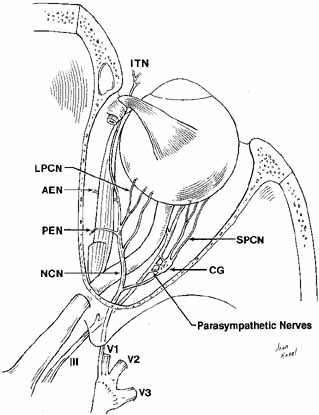

Fig. 21 Dissection to show the intraorbital nasociliary nerve course. The parasympathetic

nerve contribution to the ciliary ganglion from the inferior

division of III nerve is also shown. (V1, Vl nerve; V2, V2 nerve; V3, V3 nerve; NCN, nasociliary nerve; CG, ciliary ganglion; SPCN, short posterior ciliary nerves; LPCN, long posterior ciliary nerves; PEN, posterior ethmoidal nerve; AEN, anterior ethmoidal nerve; ITN, infratrochlear nerve) Fig. 21 Dissection to show the intraorbital nasociliary nerve course. The parasympathetic

nerve contribution to the ciliary ganglion from the inferior

division of III nerve is also shown. (V1, Vl nerve; V2, V2 nerve; V3, V3 nerve; NCN, nasociliary nerve; CG, ciliary ganglion; SPCN, short posterior ciliary nerves; LPCN, long posterior ciliary nerves; PEN, posterior ethmoidal nerve; AEN, anterior ethmoidal nerve; ITN, infratrochlear nerve)

|

exclusively. Parasympathetic Nerves The parasympathetic supply to the lacrimal gland is discussed in the previous

section on the lacrimal gland. The parasympathetics to the eye

are carried to the ciliary ganglion by a branch from the inferior oblique

nerve; they synapse in the ganglion and pass to the globe via the

short ciliary nerves. The ciliary ganglion is situated 10 mm from the

orbital apex and 15 mm behind the globe and is frequently adherent to

the lateral aspect of the apical optic nerve. The parasympathetic motor

fibers to the ciliary body and iris sphincter muscles, that originate

in the Edinger-Westphal nucleus of the oculomotor nerve, synapse

in the ganglion, in contrast to the sympathetic and trigeminal sensory

fibers that traverse the ganglion without synapse. The sensory route

from the nasociliary nerve can be found reliably, but the less well-defined

sympathetic supply may arrive from a direct branch from

the sympathetic plexus, from a twig from the ophthalmic artery, or

both.46 Five or six short posterior ciliary nerves carry fibers from the ganglion

to enter the eye around the optic nerve. The majority enter lateral